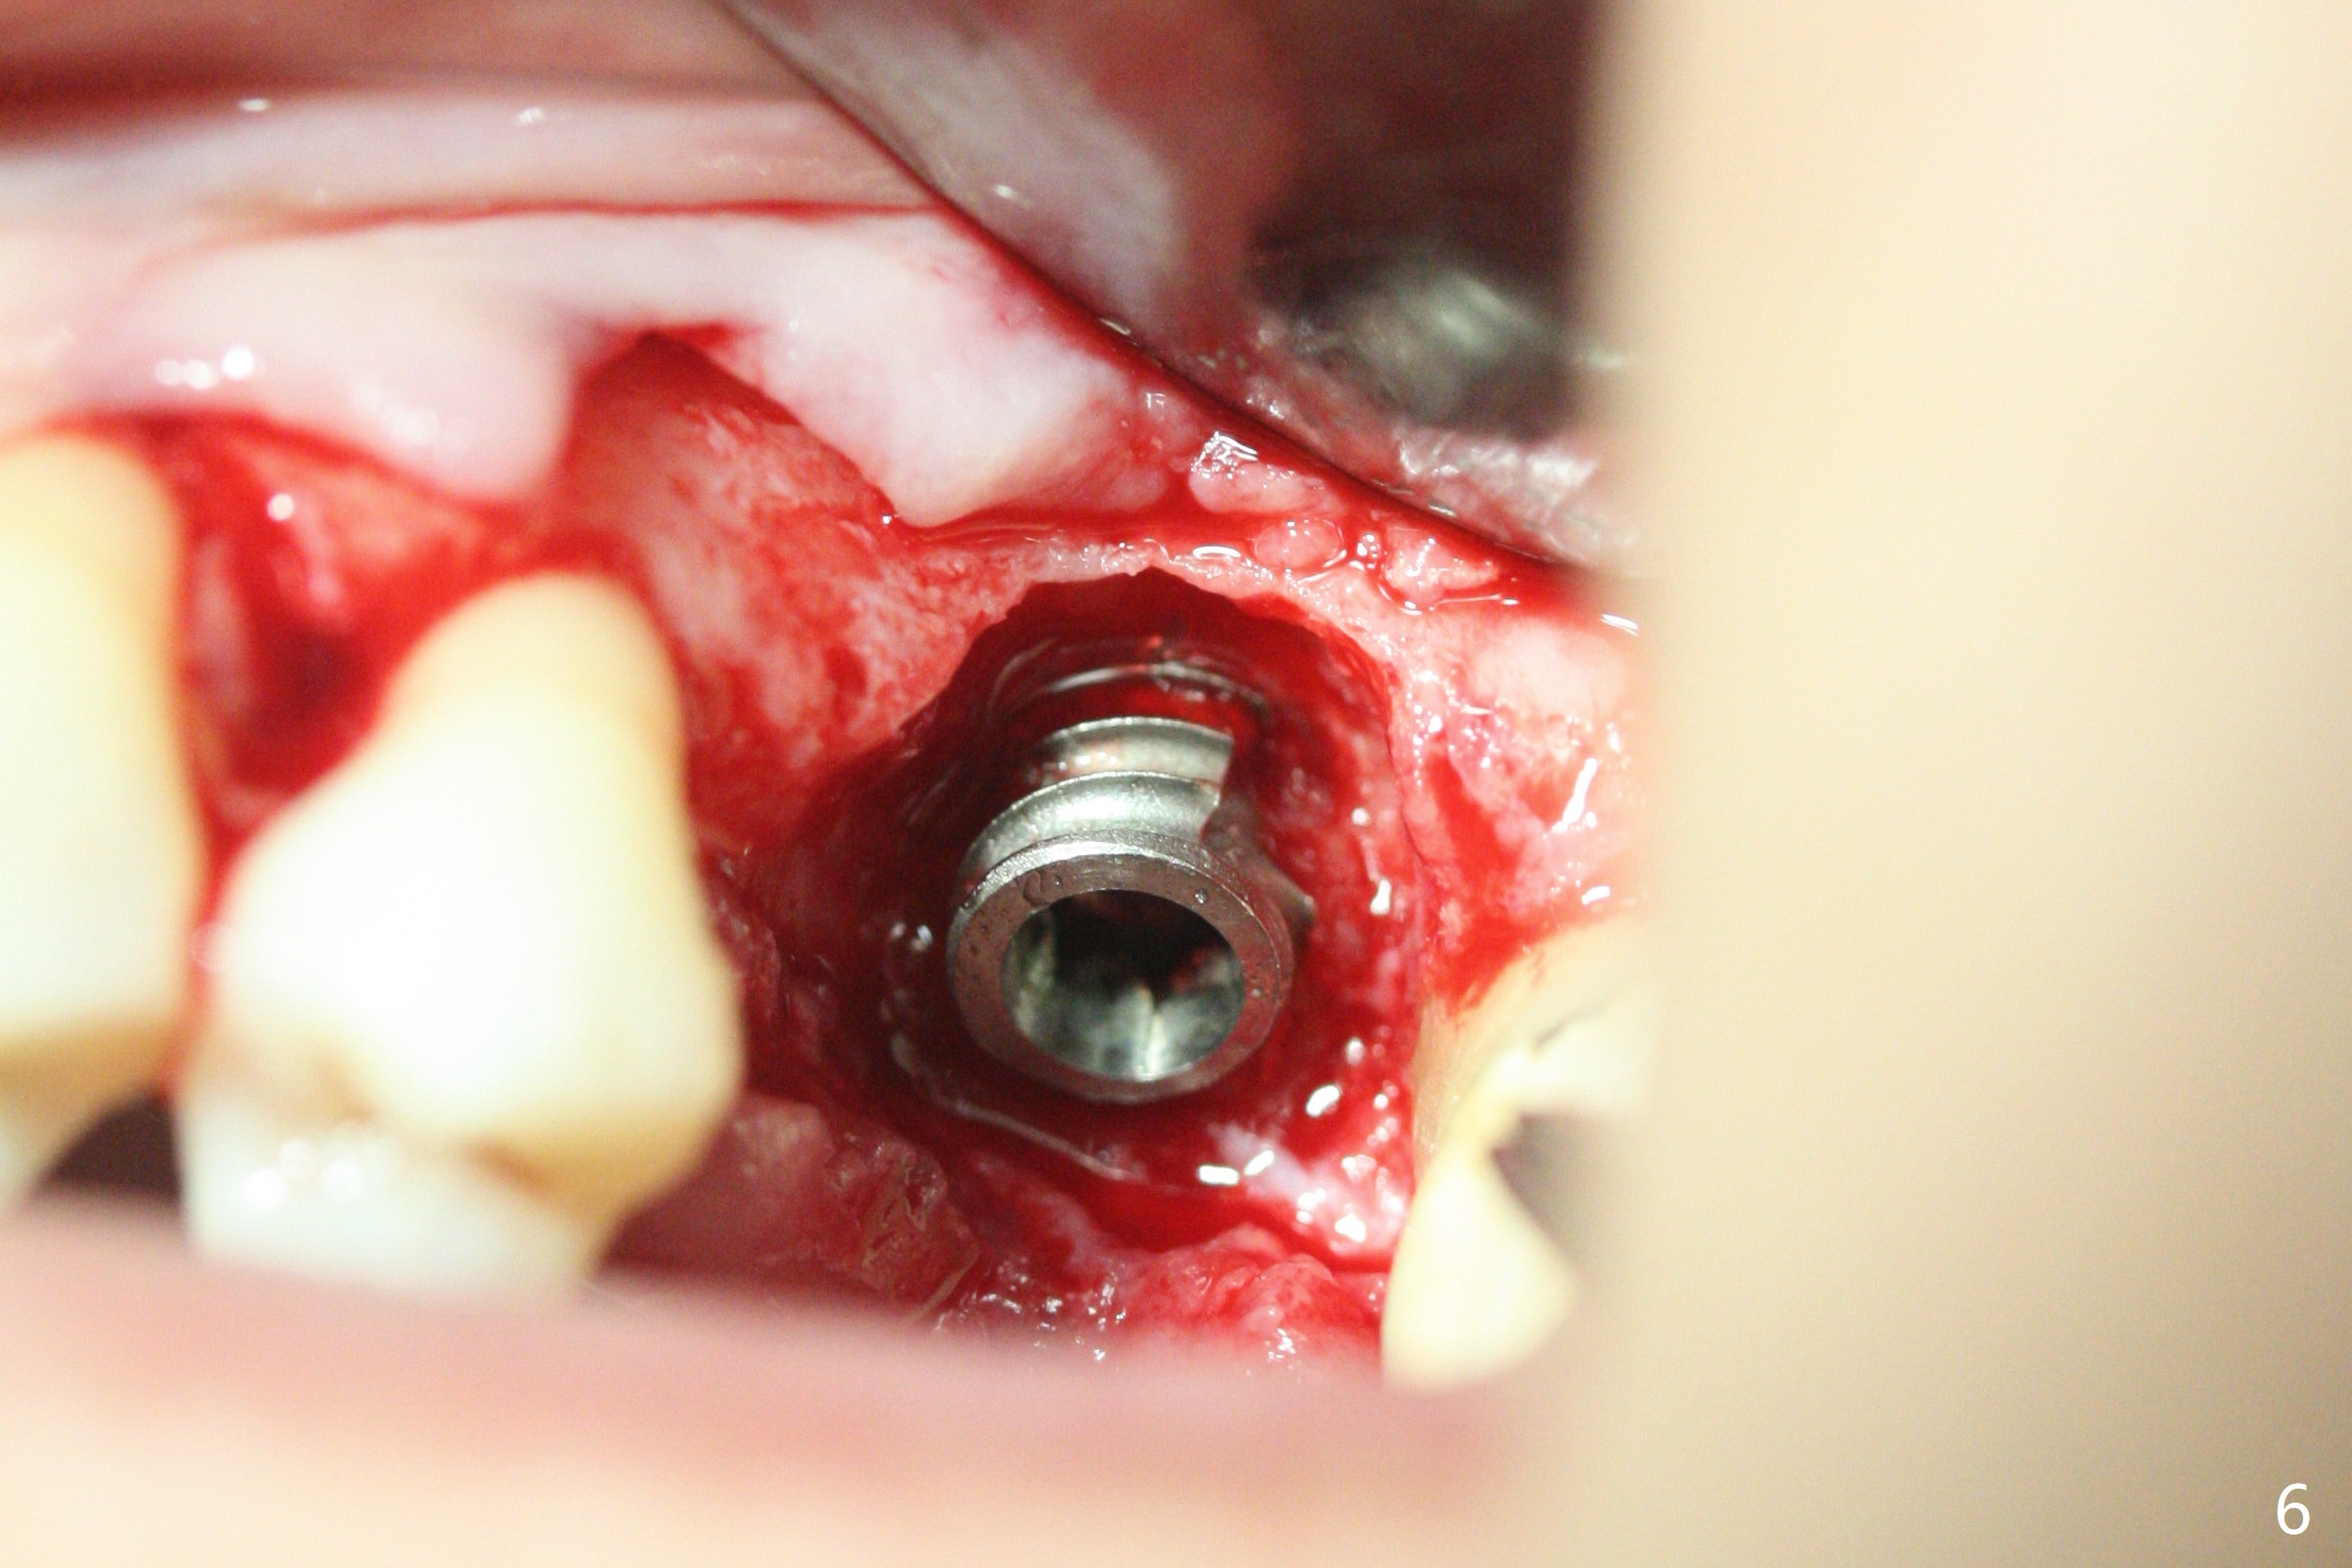

A 57-year-old woman complains of bad smell while use of water flosser between 11 and 21 months post cementation of implant crown at #14 (Fig.1,2). Bone loss is more obvious with CBCT (Fig.3,4), in spite of apparently normal gingiva around the implant after removal of the abutment and crown (Fig.5). In fact the buccal (B) gingiva is fragile with easy access to the underlying implant plateau. Following flap elevation, the bone loss is evident (Fig.6), but the implant plateau is slightly subcrestal (Fig.7 *). The exposed implant threads are covered with the 1st round of bone graft (Fig.8). After 2nd round of allograft (Fig.10-12) and collagen membrane, the flaps are approximated (Fig.9). The wound is covered by acrylic dressing. The latter is loose, but stays in place 1 week postop (Fig.13). Due to short neighboring teeth, the acrylic dressing is able to be removed with wiggling; it appears that the wound is healing (Fig.14). The dressing returns for another 2 weeks; some of the graft has been lost (Fig.15). The dressing does not return 7 weeks postop, since the wound is healing (Fig.16).